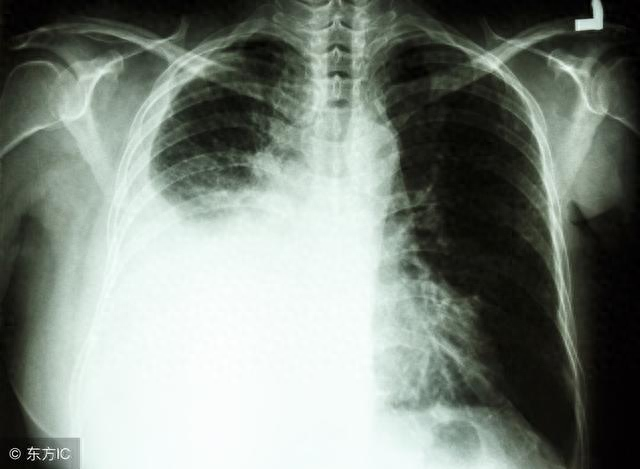

其实,肺癌在上世纪三十年代之前都是比较罕见的疾病,随着吸烟的流行,肺癌发病在上世纪中叶开始成为男性癌症病人死因的第一位。而女性肺癌病人也紧随着男性,发病率逐渐攀升。

总是可以得出,肺癌的发病是一个多因素共同作用的结果,我们能做的就是尽可能远离导致肺癌发生的外在因素,加强身体锻炼,平衡饮食,定时体检,这就是防范肺癌的最好的办法。